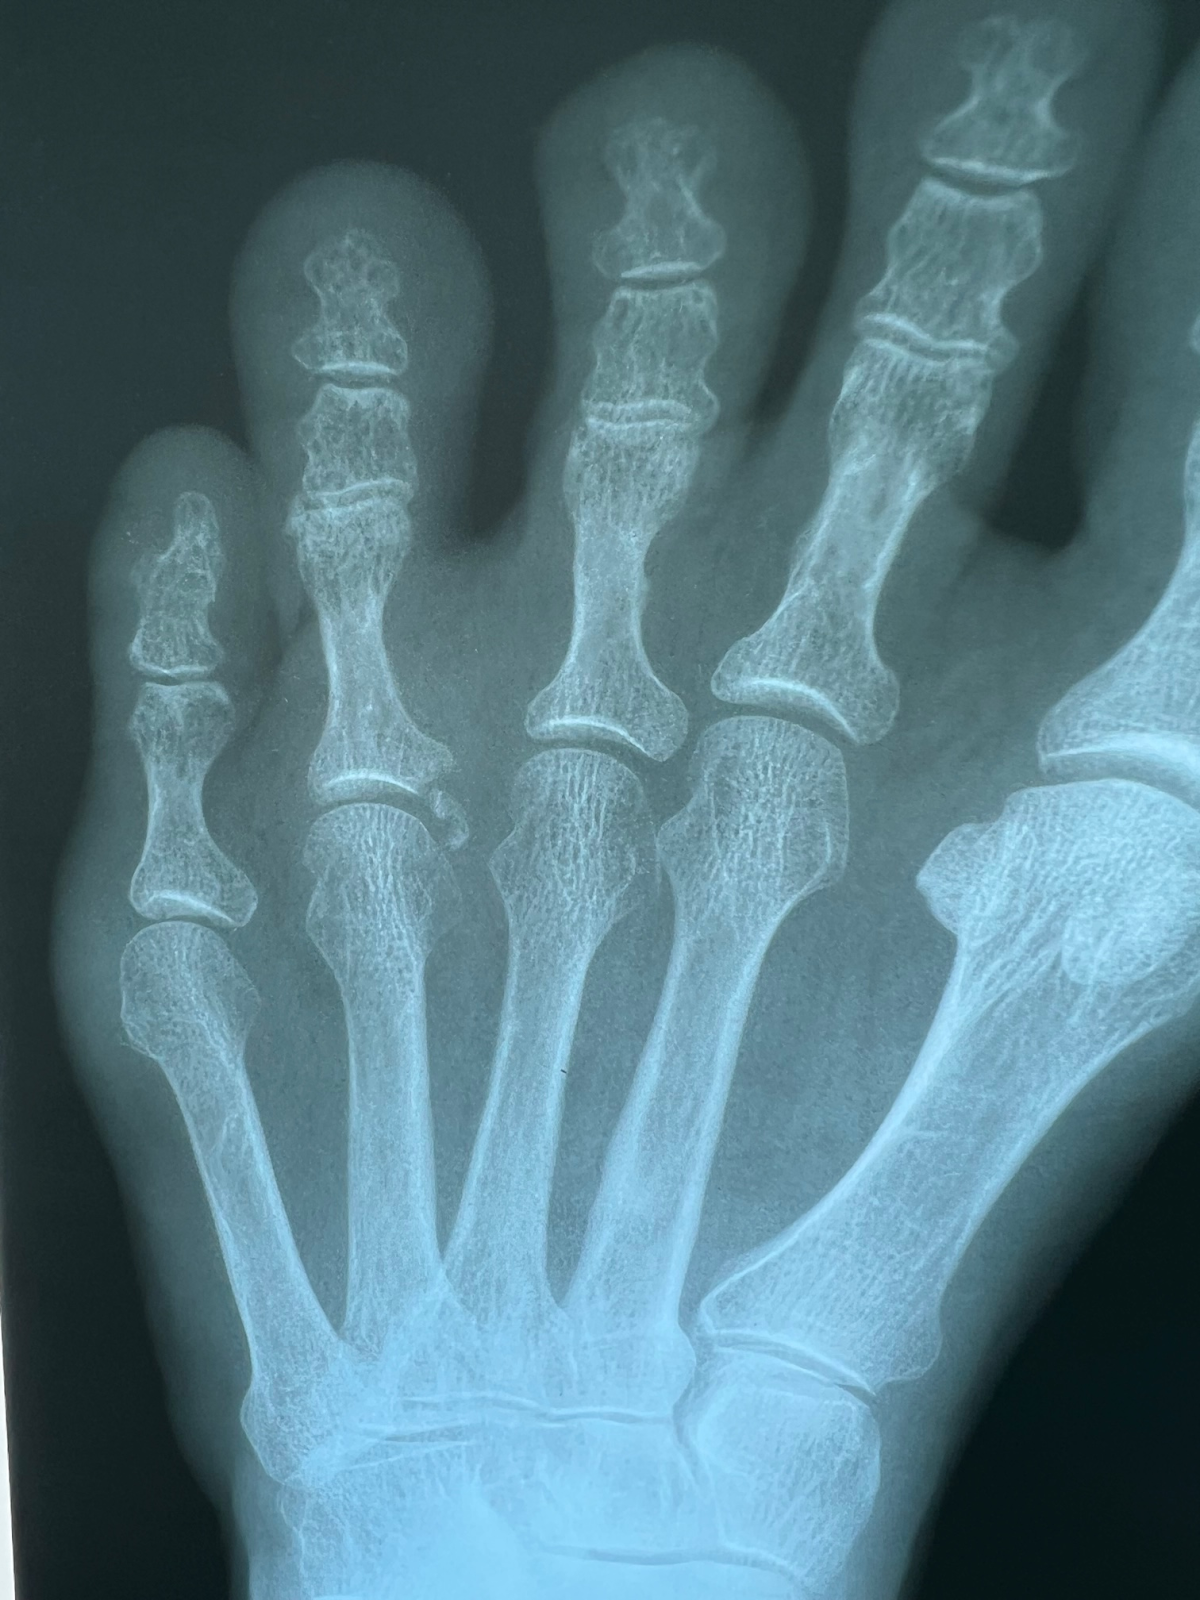

That is what the podiatrist told me when he saw the recent X-ray of my left foot. It has a small chip broken off the fourth metatarsal bone.

It happened on the Kerrville triathlon September 25; I felt a sharp pain already on the swim. Maybe I hurt myself warming up, maybe someone stepped on my foot. I have had a previous injury at the same place, something called Morton's neuroma, so I thought it was the same thing. I have actually had pain right there on and off for about two years. "Forget Morton's," said the Dr., "this is a broken bone." In hindsight, I wonder if I have had a crack for a while. Bottom line: I don't know how it happened.

When I told the podiatrist, I had completed a quarter distance triathlon with the broken foot he laughed and said I must have high tolerance for pain. There is no clear treatment, If I continue to have pain, removal of the bone chip may be the solution. For now, it is wait and see and NO RUNNING.